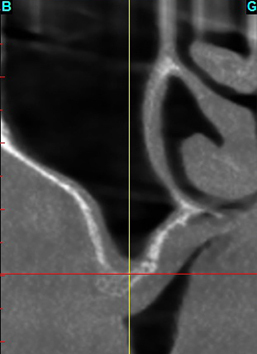

GREFFE DU SINUS: QUELLE GREFFE ?

GREFFE DU SINUS: LE COMBLEMENT SINUSIEN